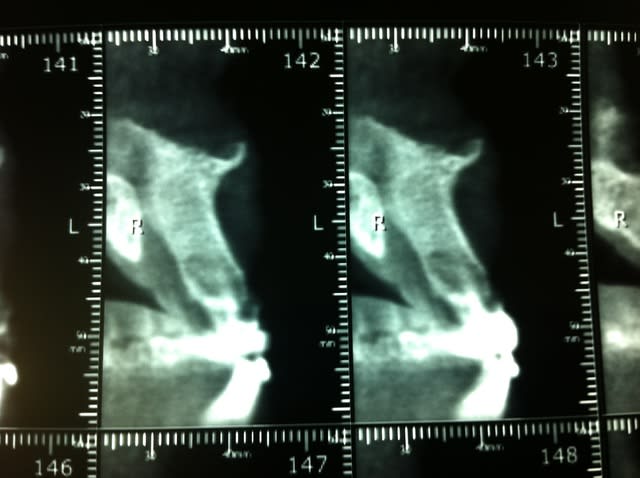

Ras à la rétro sauf un petit dépassement sur 21. Gencive tuméfiée, violacée en vestibulaire de 21-22. La 21 a déjà eu un Rte il y a 4 ans.

Rien au sondage, mais en regardant de plus prés la rétro, je suspecte un trait de fracture en distal de 22...

Mis sous Antibio, plus de signe clinique. Prescription de cone Beam et surprise, belle image...